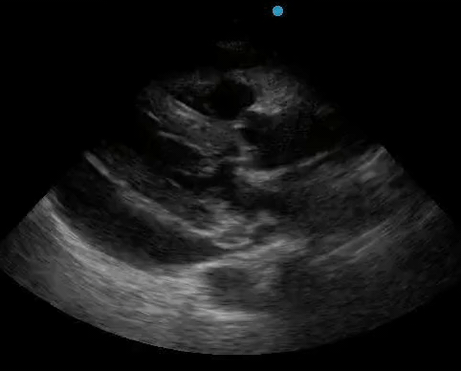

Historically, cardiac tamponade was diagnosed as a constellation of clinical findings, including Beck’s triad (hypotension, jugular venous distention, muffled heart sounds), pulsus paradoxus, and electrical alternans on electrocardiography. However, studies have demonstrated that the clinical history and physical exam perform poorly, with the sensitivity of Beck’s triad being 0% in one review.5 Furthermore, vital sign derangements are also not reliable predictors of tamponade; tachycardia was only present in 59.5% of patients, while hypotension was only present in 31.4%.5 Thus, point-of-care echocardiography should be used to confirm the presence of pericardial effusions and secure a diagnosis of tamponade. Although trivial and small effusions may be difficult to visualize, moderate to large pericardial effusions are easily identified as fluid collections surrounding the myocardium in the subxiphoid view. On parasternal long views, pericardial effusions may be visualized anterior to the right ventricular free wall and posterior to the LV, crossing in front of the descending aorta (Figure 1). While serous pericardial effusions are typically hypoechoic and readily identified as a fluid-filled space, hemorrhagic or purulent effusions may be heterogeneous and similar in appearance to a generous pericardial fat pad, although fluid motion is likely to be seen.4

Figure 1. A) Subxiphoid cardiac view, demonstrating a moderately-sized pericardial effusion. B) Parasternal Long Axis cardiac view, demonstrating a moderately-sized pericardial effusion which tracks anterior to the descending aorta.